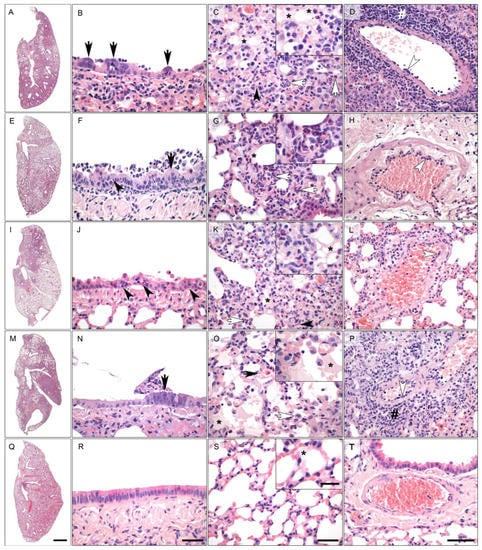

3.3. Histopathology of Lung Tissue after Infection with SARS-CoV-2

3.4. Inflammation Score of Lung Histopathology